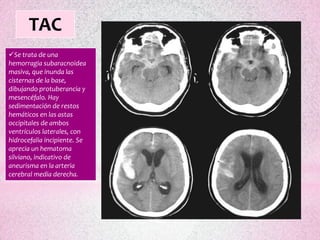

TAC

Se trata de una

hemorragia subaracnoidea

masiva, que inunda las

cisternas de la base,

dibujando protuberancia y

mesencéfalo. Hay

sedimentación de restos

hemáticos en las astas

occipitales de ambos

ventrículos laterales, con

hidrocefalia incipiente. Se

aprecia un hematoma

silviano, indicativo de

aneurisma en la arteria

cerebral media derecha.